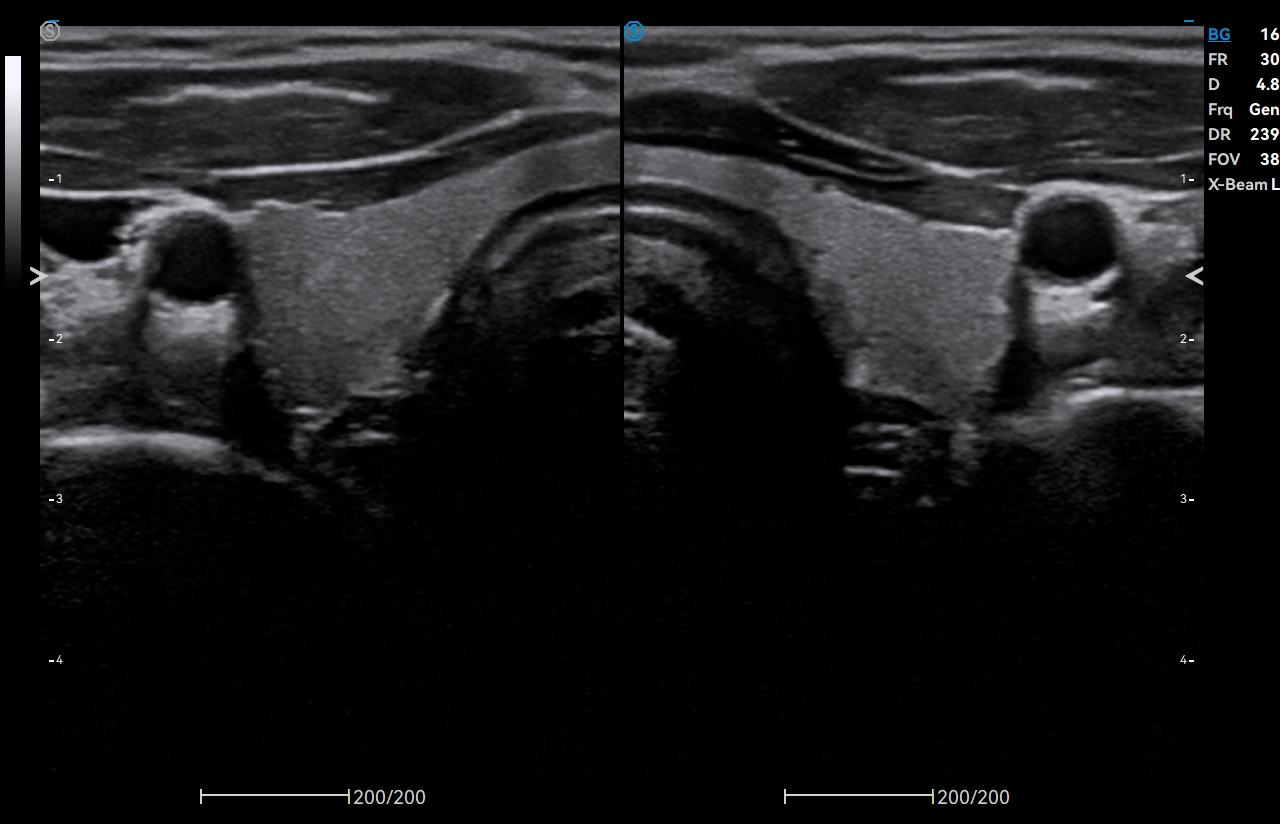

- Category: Color Doppler

Click on images to enlarge

Click on images to enlarge